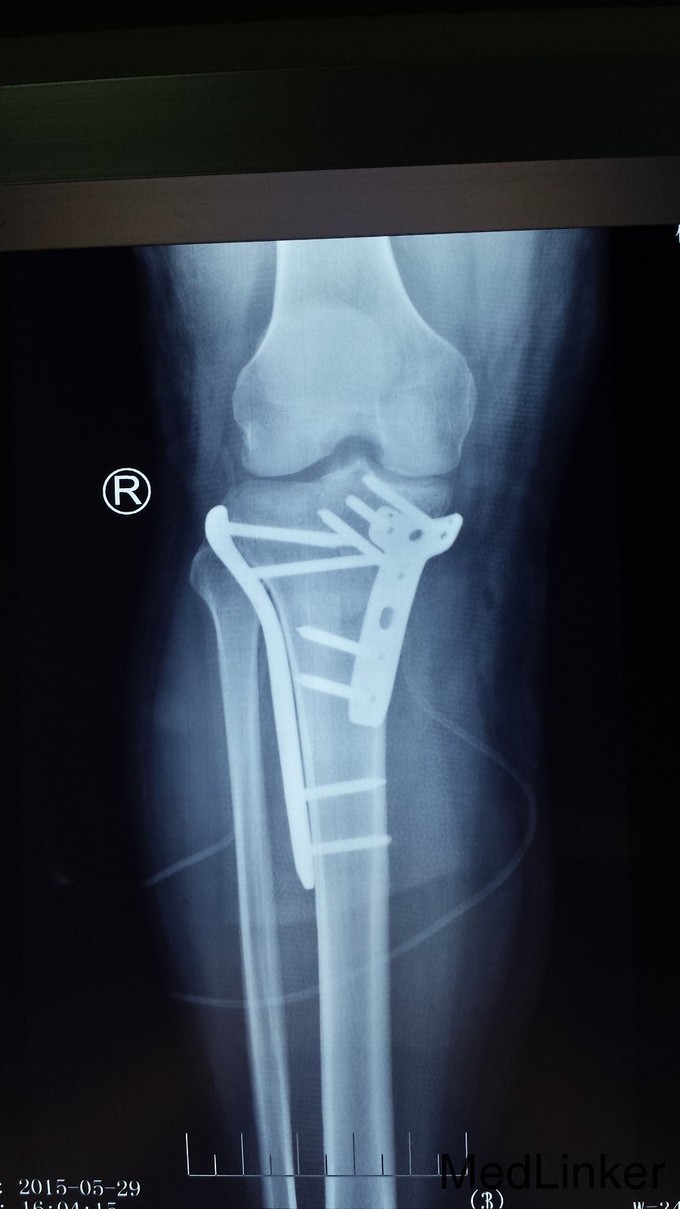

光片提示:患者发生累及后内踝的平台骨折。急诊:施行后内、前外侧联合入路手术治疗。先作后内侧入路复位后内髁骨折块及内髁骨折,再作前外侧联合入路复位外髁骨折,同时处理半月板及前、后交叉韧带损伤。

胫骨平台骨折是较为严重的骨折。如诊治不当,会导致股骨髁向后半脱位,造成膝关节不稳、疼痛、及退行性变,致膝关节功能障碍。因此治疗时要注意关节面解剖复位、坚强内固定及塌陷骨植复位。胫骨平台骨折完全恢复一般需六个月,因此进行功能锻炼要循序渐进。过早或过量运动容易造成平台塌陷。早期应增强无负重的肌肉锻炼,多做坐踢腿动作,促进关节血液循环,帮助恢复。